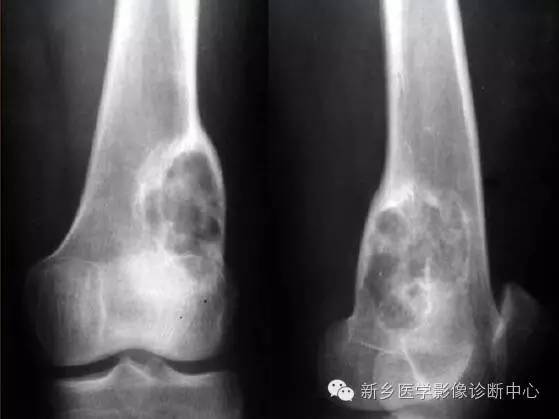

骨良性纤维组织细胞瘤(benign fibroushistiocytoma,BFH)是原发于骨的间叶肿瘤,属于世界卫生组织(WHO)分类中组织细胞源性肿瘤。纤维组织细胞瘤常见于软组织中,极少数起源于骨中,但两者具有相同的组织学表现。良性纤维组织细胞瘤具有纤维母细胞与组织细胞分化特点,与骨干骺端非骨化性纤维瘤在组织学上相似,但是具有不同的临床和放射学特点。

临床特征:发生于成人,男女发病率无明显差别。全身骨骼均可发生,但以四肢长骨居多,尤以股骨、胫骨多见。发生于干骺端多见。其余报道发生于长骨骨干、骨盆、肋骨、指(趾)骨、颈椎及上颌骨。临床表现通常以局部疼痛为主,有时可并发病理性骨折。本病具有局部侵袭性,手 术刮除后可局部复发,出现进展性骨破坏,但不转移。

影像学特征:病变均为溶骨性,边界光滑,多数有硬化缘,内部可见粗糙骨小梁。在长骨,可起源于骨干及干骺端,后者累及骨骺多见。初期,病变位于骨髓腔内,偏心性生长,随病变进展,骨皮质受侵变薄,可出现病理性骨折。

临床及影像特征:(关于骨良性纤维组织细胞瘤图片分析,见上图)1.年龄及病史:女性,32 岁,右膝关节疼痛一年2.病变的部位:右侧股骨内髁及干骺端3.病变的数目:单发,偏心性4.骨破坏的类型:地图样破坏,无明显膨胀性,其内未见骨嵴5.病变的边缘:边界清楚,可见硬化带6.病变基质的类型(肿瘤组织的成分):肿块内未见骨性及软骨性钙化。7.骨皮质改变:未见破坏。8.骨膜反应:未见明显骨膜反应9.软组织肿块:未见

① 骨巨细胞瘤:多呈膨胀性、偏心性骨质破坏,多房性骨破坏,骨皮质变薄,无骨硬化与骨膜反应,发生于膝关节周围,多累及骨端,血管造影多数有轻度至中度血运增加,均与良性纤维组织细胞瘤不同;组织学主要为纤维黄色组织,呈旋涡状,可见多核巨细胞及泡沫细胞,巨细胞较大且核数较多;而BFH梭形细胞和多核巨细胞体积较小,分布较稀疏,核数较少,泡沫细胞较多本组病例均发生于骨端,呈边界清楚的膨胀性溶骨性破坏术前误诊为骨巨细胞瘤,确诊须依靠病理。